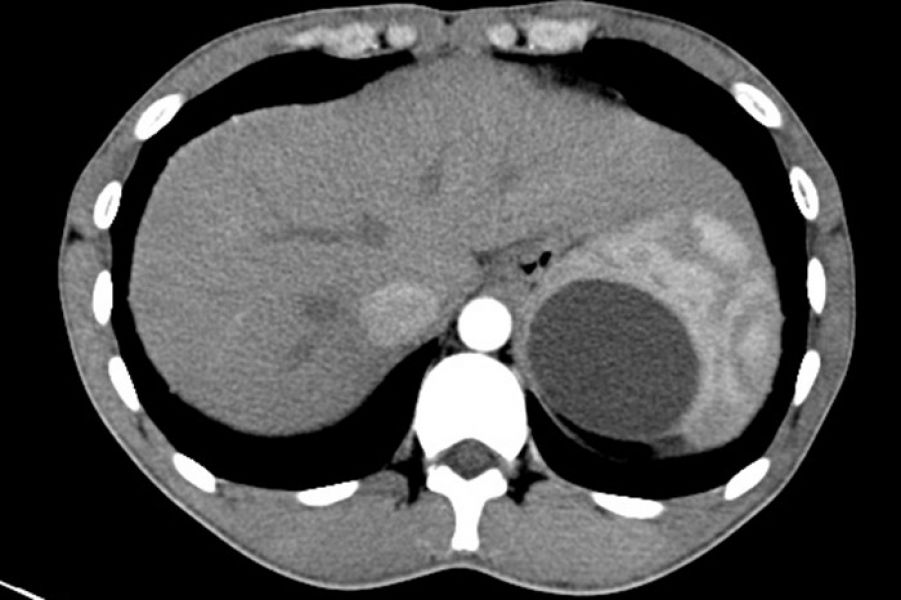

患者向某某,18岁,学生,于7月9日以“体检发现左上腹肿块4月要求手术”为主诉入院。患者4月前在当地医院行高考前体检,腹部彩超检查发现“左上腹一囊性包块,性质来源待定”。高考结束,在我院门诊进一步行上腹部CT检查,结果报告:“脾上极一囊性占位,大小约6.5*5.3cm”,门诊以“脾囊性占位”收住肝胆外科一病区。

术前CT